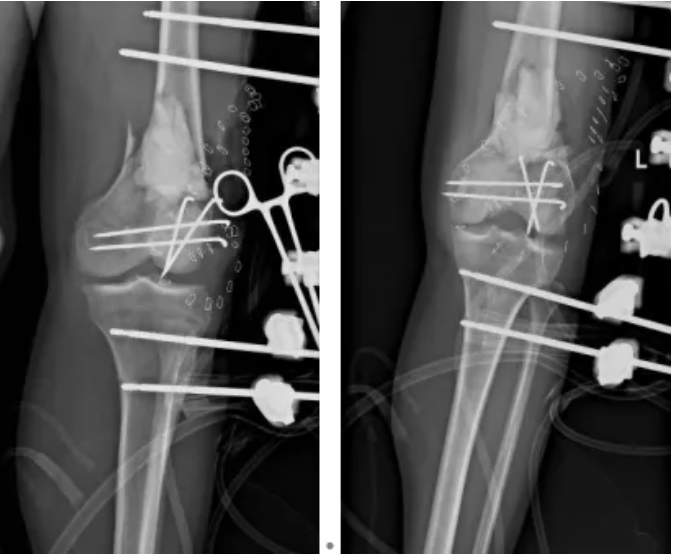

“生命至上” 是救治的核心原则。医院立即启动多学科协作机制,骨科牵头联动影像科、重症监护室、心胸血管外科、麻醉手术科等多科室,快速制定个体化分期治疗方案。到院当晚,急诊手术率先开展:对左膝部开放性伤口彻底清创,因骨质缺损多且污染严重,术中创新性使用抗生素骨水泥填充缺损区域,同时以外固定架临时固定左下肢,并行右胫骨骨牵引术。

开放性骨折尤其是 Gustilo ⅢB 型骨折,合并严重骨与软组织缺损时,术后感染、肢体坏死甚至截肢风险极高。传统清创后低剂量细菌仍可能残留,易形成细菌生物膜引发感染。而抗生素骨水泥可直接规避细菌黏附与生物膜形成,同时局部释放高浓度抗生素,杀灭伤口周围细菌,为内固定物提供 “自净保护”,有效降低感染率、促进创面愈合。

6月9日,为患者实施右股骨、左桡骨、腰 1 椎体爆裂性骨折复位内固定术,同时对左股骨远端开放性骨折再次清创,确认伤口无感染迹象,基底长出新鲜肉芽组织;